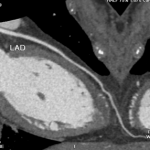

女性,43歲,心跳速率每分鐘56下,BMI: 20 顯影劑速率4.0ml/s 總量 67ml/輻射劑量1.9mSv